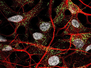

Pain Pathway

The brain's emotional (distress caused) pain pathway identified – offering new targets for developing pain medication

This group of neurons (green) within a subsection of the brain's thalamus are a newly discovered part of the circuitry that links the physical sensation of pain to the emotional response. It's the emotional aspect of pain – the distress it causes – that teaches an animal to avoid potentially painful situations. Indeed, when carefully targeted genetic techniques were used to deactivate this particular group of neurons in mice, the animals could still sense the pain of heat or pressure but didn't learn to avoid the source of the stimulus. By contrast, when these neurons were artificially activated, the mice exhibited distress and avoidance behaviours even in the absence of actual pain stimuli. The identification of this emotional pain pathway offers new targets for developing different forms of pain medication that might be especially useful for people with increased sensitivity to pain or with chronic and distressing pain disorders.